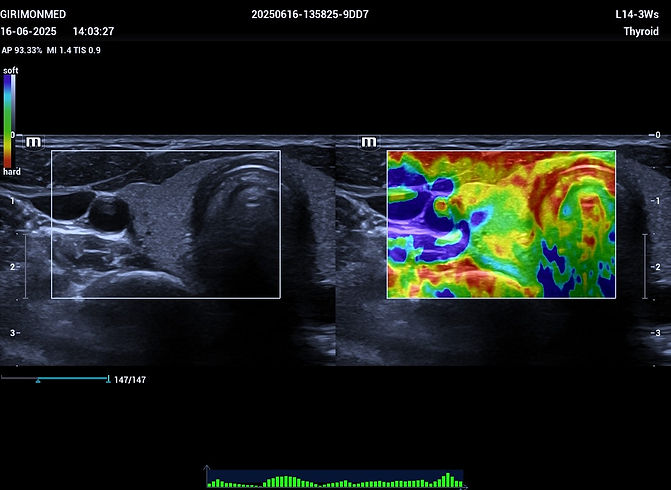

הפרעות בבלוטת התריס (היפותירואידיזם, היפרטירואידיזם, גושים)